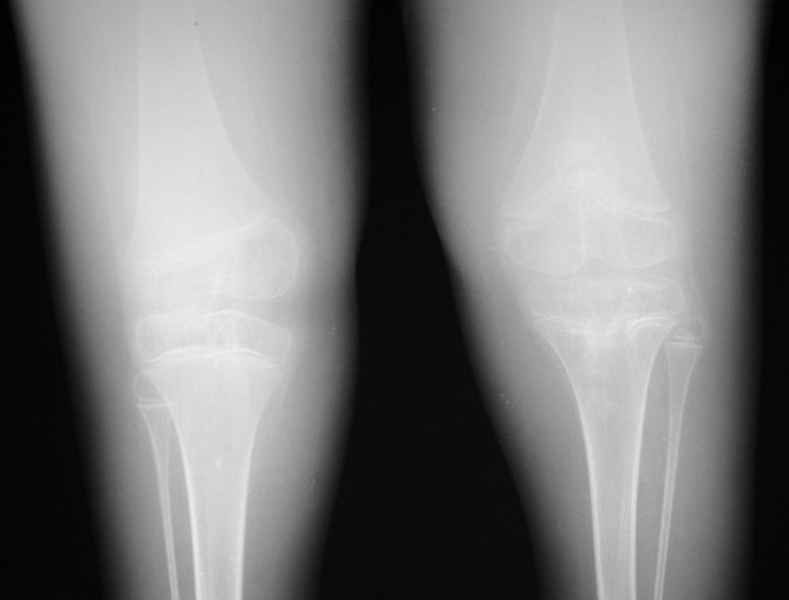

Диагноз. Артрогрипоз. Врожденные двусторонние вывихи бедер. Рецидивирующая двусторонняя врожденная косолапость тяжелой степени (состояние после оперативной коррекции в 2004 году с обеих сторон). Мягкотканные разгибательные контрактуры коленных суставов. Атрофия мышц голеней. Значительное нарушение функции нижних конечностей.

Место болезни. Передвижение ребенка резко нарушено, нижние конечности имеют атрофированный вид, мышцы голени дряблые, истончены. Форма всех суставов нижних конечностей деформирована. Коленные и тазобедренные суставы в положении разгибания. Сгибание и разведение тазобедренных суставов резко ограничено, имеет место их выраженная приводящая контрактура. Сгибание коленных суставов возможно до 90 , но при этом отмечаются болевые ощущения. Со слов мальчика: он боится сгибать коленные суставы из-за имевших место болезненных подвывихов голеней кнаружи. Клинически определяется невыраженная нестабильность коленных суставов - патологическая подвижность кнаружи (больше слева). Правая нижняя конечность короче левой на 8 см. Скарповские треугольники расширены. Ягодичные области симметричные. Ромб Михаэлиса симметричен, Явной деформации позвоночника не выявлено (в положении лежа и сидя). Оба коленных сустава деформированы, незначительно вальгированы (до 10 ), сгибание их резко ограничено. Стопы и голеностопные суставы деформированы, имеются п/о рубцы цвета кожи по задней и внутренней поверхностям голеностопных суставов и стоп. Сохраняется выраженное эквиноварусное положение обеих стоп, выведение их в правильное положение не возможно: приведение передних отделов стоп до 45 , супинация 45-50 , эквинус более 90 , движения качательные.